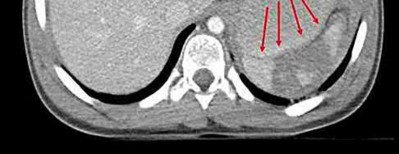

Question 19

A 28-year-old male sustains a closed comminuted tibial shaft fracture.

Two hours post-injury, he develops severe leg pain unyielding to narcotics. His blood pressure is 120/80 mmHg. Intracompartmental pressure monitoring is performed. Based on current guidelines, which measurement dictates an emergent 4-compartment fasciotomy?

Explanation

Acute compartment syndrome is classically defined by tissue hypoperfusion. The absolute compartment pressure is less reliable than the differential pressure (Delta P). A Delta P (Diastolic Blood Pressure minus Compartment Pressure) of less than 30 mmHg is an absolute indication for emergency fasciotomy, as capillary perfusion gradient is lost when tissue pressure approaches the diastolic pressure.